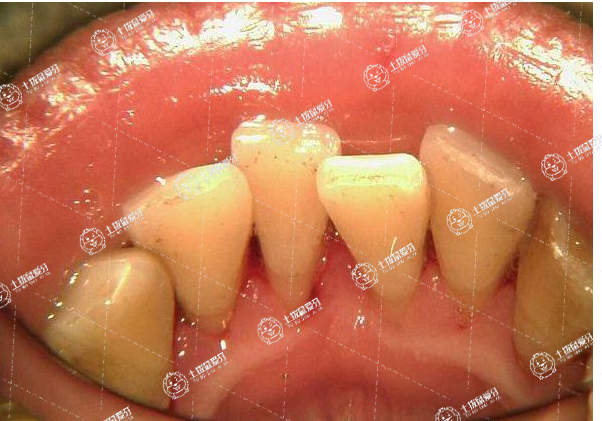

近些年來(lái),很多兒童在生活當(dāng)中牙齒畸形問(wèn)題可以說(shuō)是越來(lái)越嚴(yán)重,特別是牙齒稀擁擠問(wèn)題,作為家長(zhǎng),發(fā)現(xiàn)孩子的牙齒擁擠問(wèn)題越來(lái)越影響孩子的容貌,長(zhǎng)時(shí)間不及時(shí)矯正的話,往往就會(huì)進(jìn)一步給孩子的身心健康造成一定的影響,兒童牙齒擁擠有沒(méi)有必要矯正?對(duì)此,接下來(lái),我們一起來(lái)了解一下。

8歲兒童牙齒擁擠,建議先觀察,不要急于矯正。此時(shí)由于正處于換牙期,牙齒畸形和擁擠的發(fā)生一般是暫時(shí)的,可以通過(guò)頜骨發(fā)育來(lái)調(diào)節(jié)。牙齒矯正一般等11~12歲時(shí)再進(jìn)行。

8歲小孩的齒列在增長(zhǎng),出現(xiàn)錯(cuò)頜畸形而擁擠,通常是暫時(shí)的,可以通過(guò)改掉不良習(xí)慣,多咀嚼堅(jiān)硬的食物,刺激下頜生長(zhǎng),一般輕微的擁擠就可以矯正。正畸治療要等到恒牙替換后。

但也有一些情況需要矯正,如換牙過(guò)程中出現(xiàn)異常萌出和換牙,或因齲齒導(dǎo)致牙齒過(guò)早脫落,就要及時(shí)去醫(yī)院,防止更嚴(yán)重的牙齒擁擠。對(duì)于一些普通擁擠,一般可以在(11~12)歲以后再來(lái)矯正。

8歲兒童牙齒擁擠建議及時(shí)就診,遵醫(yī)囑進(jìn)行治療,以免延誤病情。